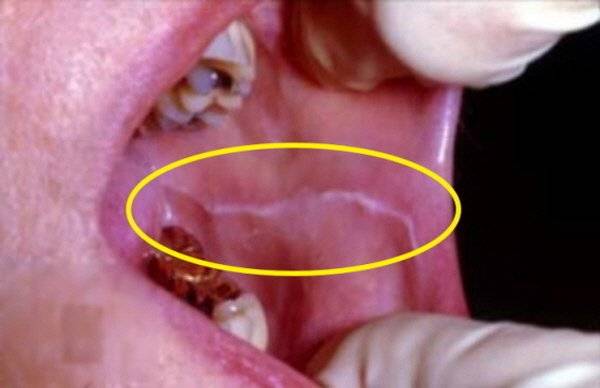

부드럽고 매끈한 속살은 온데간데없이, 이렇게 볼 안쪽에 하얀 가로줄이 생겨 있을 경우 나의 치아 습관을 한번 돌아보시는 게 좋겠습니다. 이 하얀 줄의 정체는 바로 '백선'. 이를 갈거나, 악물거나, 음식을 먹을 때 볼살을 함께 씹는 습관 등으로 인해 생기는데요.

별다른 통증도 없고, 방치해도 아무 문제가 없어서 평소에는 그 존재마저 모르는 경우가 많지만 치아에 안 좋은 습관이 반영되어 있기 때문에 가급적 고치시는 게 좋겠습니다.

백선을 만들어내는 이갈이나 이 악물기는 치아와 턱관절에 있어 치명타인데요.

혹시 '어? 난 가로줄이 아니라 그물 모양으로 나 있는데?' 하는 분이 계시다면 '편평 태선'이라는 염증성 질환일 수 있는데요.

스트레스나, 진통제·당뇨약 등 특정 약물의 부작용으로 인해 100명 중 1명꼴로 나타나는 흔한 질환이지만, 심하면 구강암으로 번질 수도 있다고 하니 꼭! 가까운 구강내과에 찾아가 진단을 받아보시기 바랍니다!